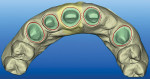

There are currently four proven systems offering intraoral digital impression capabilities, all of which produce an augmented versus a virtual reality image. In an augmented image, the virtual and real worlds are combined. The user does not wait for an impression cast in dental stone to set, but instead has an instant 3-dimensional (3-D) replica available as soon as the recording is completed (Figure 1).

These four systems are the Lava™Chairside Oral Scanner C.O.S. (3M ESPE, www.3MESPE.com), iTero™digital scanner (Align Technology, Inc., formerly Cadent Inc., www.cadentinc.com), CEREC® (Sirona Dental Systems Inc., www.sirona.com), and E4D Dentist™(D4D Technologies, www.e4d.com). Lava C.O.S. and iTero are currently the only stand-alone digital scanning systems not linked to an in-office restoration milling unit. In contrast, the CEREC and E4D digital scanning systems have software restoration design capabilities and are mated to an in-office ceramic block-milling unit. Thus, two intraoral “information gatherers” and two CAD/CAM restoration producers are in use today.

While each distinctly unique, both the Lava C.O.S. and iTero digital scanners—upon which this article will focus—produce an augmented versus a virtual reality image. Both capture the visible tooth and tissue structures in detail that surpasses or equals elastomeric impression materials. Both systems allow the user to transmit the data file via e-mail in an STL format for fabrication of accurate, articulated CNC 5 axis milled or stereolithography (SLA) plastic polymer casts to fabricate dental restorations. (STL is an interchange file format used for rapid prototyping technology to produce 3-D parts; it is used to save CAD files in a standard format that can be read by multiple CAD applications.) Both require a case fee for data transmittal and working model assembly. Single-unit, multiple-unit, complete-coverage, and partial-coverage restorations as well as inlays may be made from the data with either system. The purchase price of the Lava C.O.S. and iTero scanners is similar. Dentists and dental auxiliary can easily learn to use these digital scanners in 1 to 2 days of in-office, manufacturer-